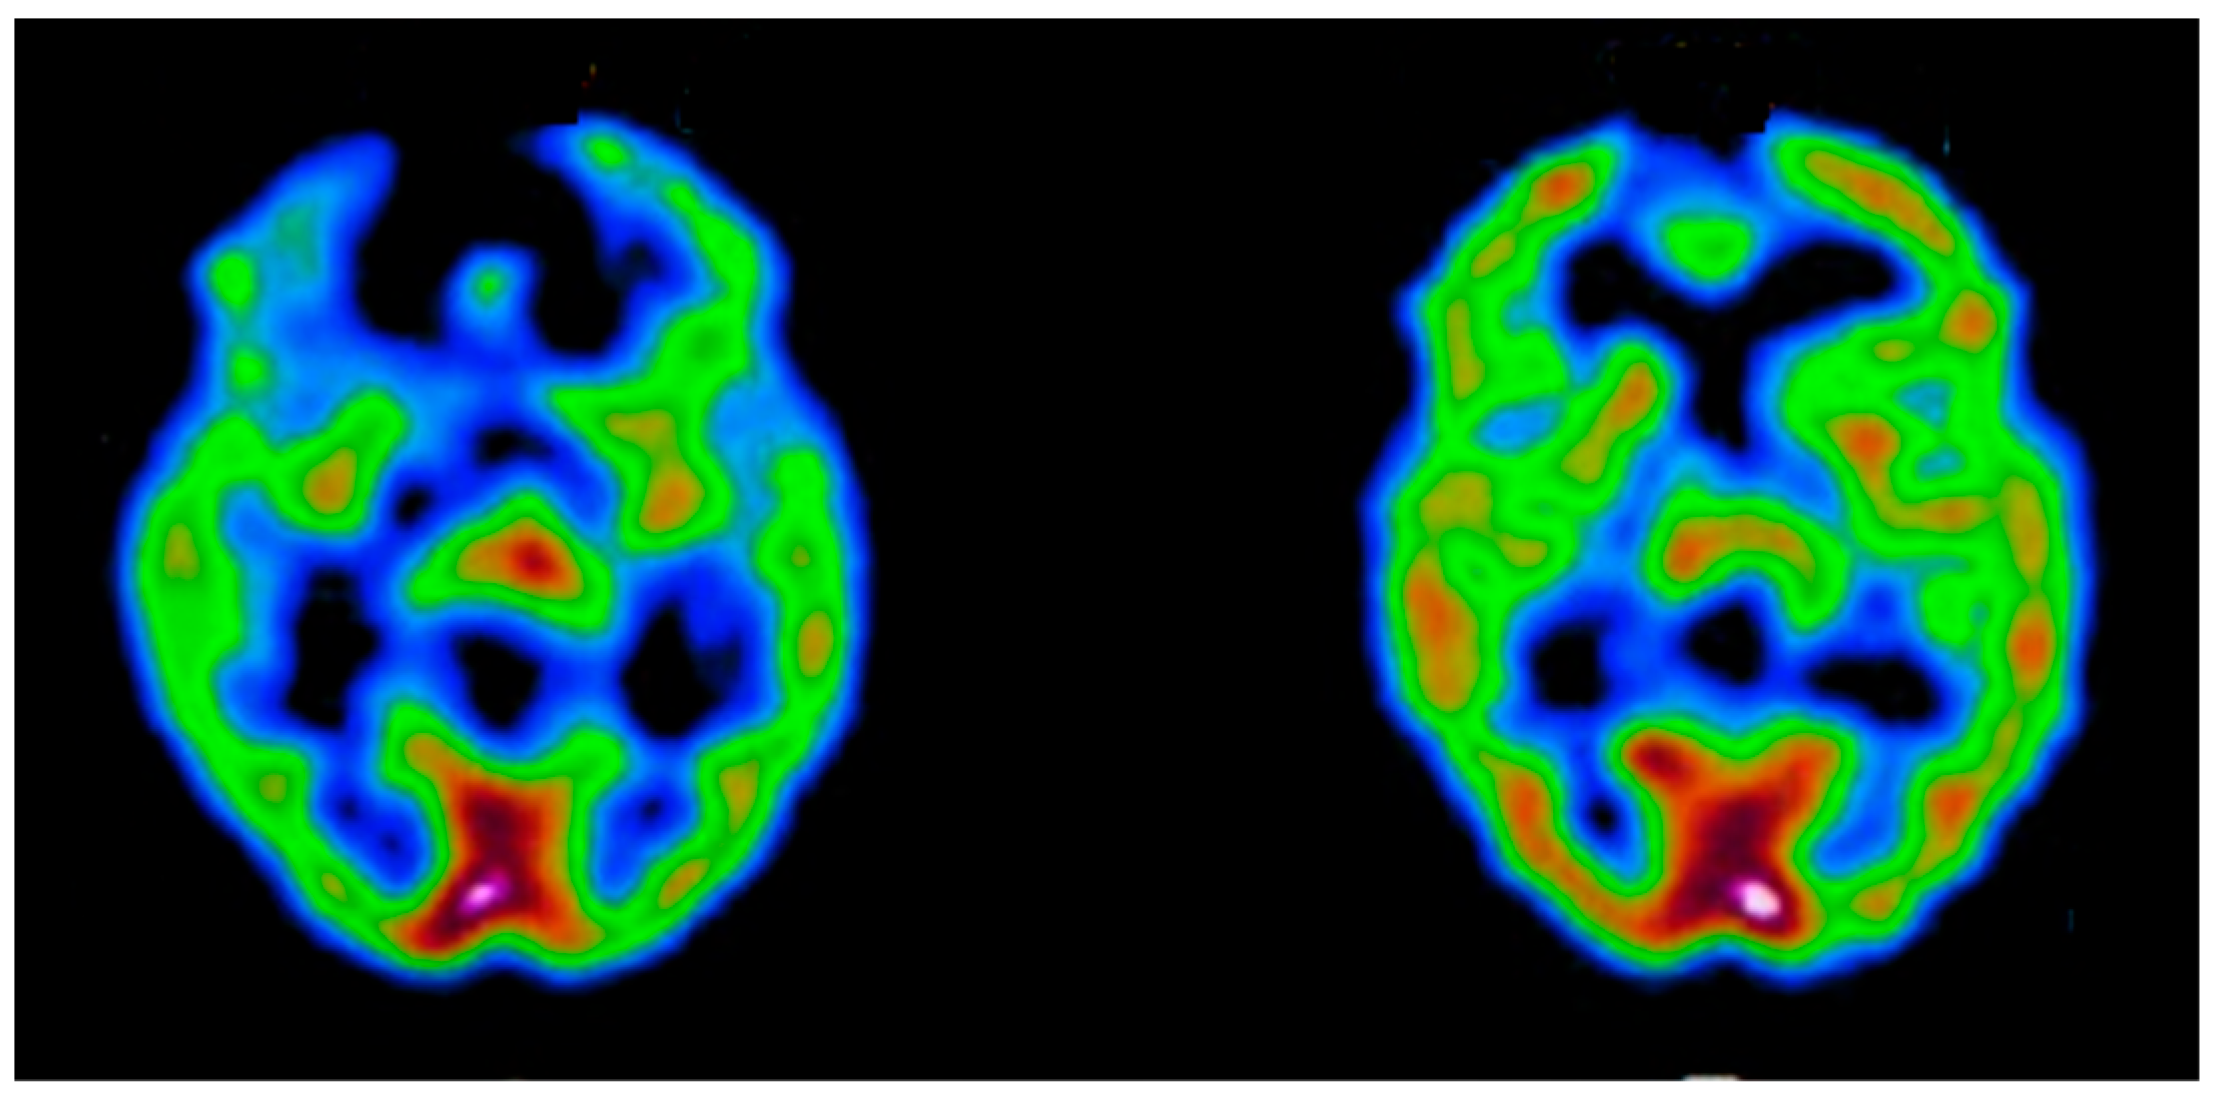

Appendix B.2.3. Single-Photon Emission Computed Tomography (SPECT)

- Catafau, A.M. Brain SPECT in clinical practice. Part I: Perfusion. J. Nucl. Med. 2001, 42, 259–271. [Google Scholar] [PubMed]